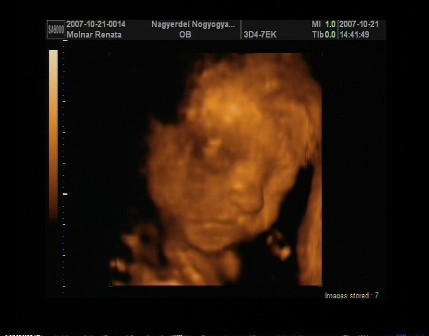

reni, na azt elhiszem hogy be vagytok már sózva az uh miatt!